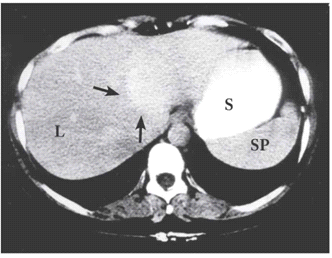

בטומוגרפיה ממוחשבת ניתן לראות מילוי של חומר ניגוד בהמנגיומה (תצלומים 15.10-17.10).